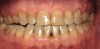

Figure 3

Figure 3 through Figure 7 Preoperative retracted, occlusal, and lingual views. Note the extreme acid erosion, with lost occlusal and lingual enamel.